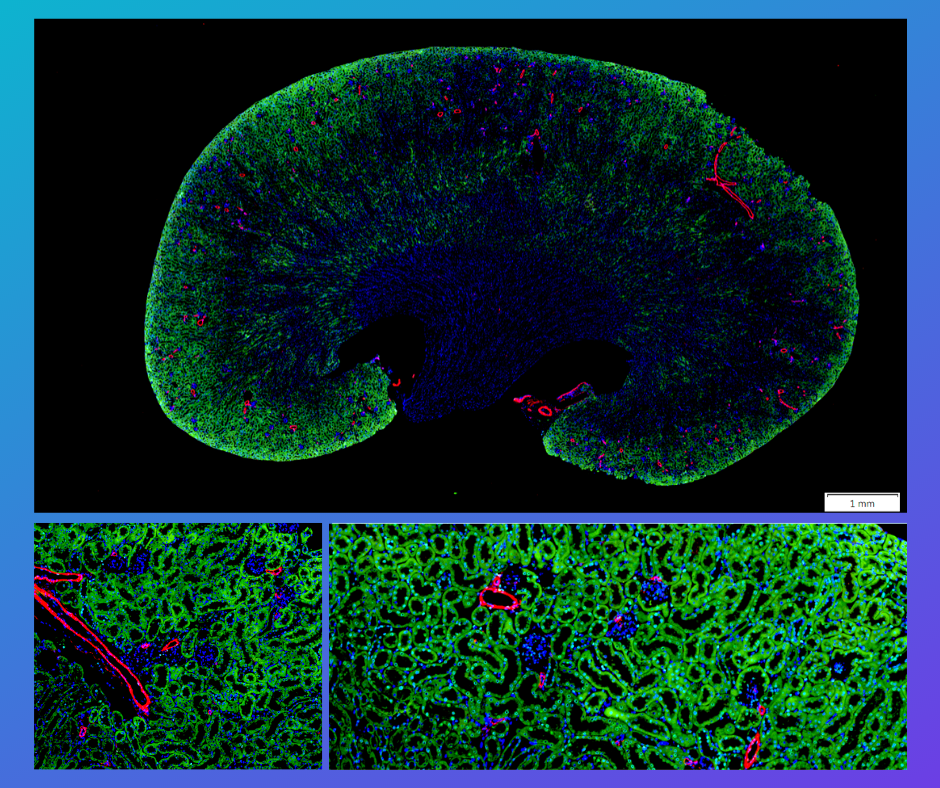

免疫螢光染色服務 (immunofluorescence, IF)

免疫螢光染色 (Immunofluorescence, 以下簡稱IF) 是生物學中一種常用工具,主要通過使用抗體來可視化蛋白質的表達、分佈和位置轉換,並利用顯微鏡進行觀察。

常規免疫螢光是將螢光染料與二抗偶聯,利用二抗來辨識一抗並與之結合 (間接 IF),通常用於檢測細胞或組織中的單一抗原。 拓生科技-使用獨家代理的 #BioTnA - Tools of molecular pathology 螢光染色套組,超清楚的訊號、乾淨的背景,並搭配病理核心實驗室成熟的染色技術,讓不同的markers都可以在同一片組織上清晰的表現。

上圖-使用 BioTnA #TATS01,螢光染色套組,所染色出來的實際效果。

Tissue Microarray (TMA) 組織微陣列切片螢光三染-THTS01-Fluorescence multiple stain kit